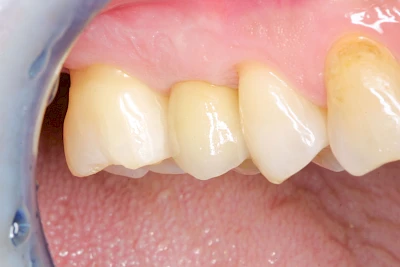

Fehlen einzelne Zähne und die Nachbarzähne sind unbeschadet oder gut zahnärztlich versorgt, werden immer häufiger Implantate gewählt, um die Lücken zu schließen. Auch bei größeren oder verteilten Lücken, wenn keine herausnehmbare Prothese gewünscht ist, werden Implantate für Kronen- bzw. Brückenversorgungen gesetzt. In Einzelfällen entscheiden sich sogar zahnlose Patienten für eine festsitzende Versorgung auf Implantaten.

Varianten zur Verankerung von festsitzendem Zahnersatz auf Implantaten